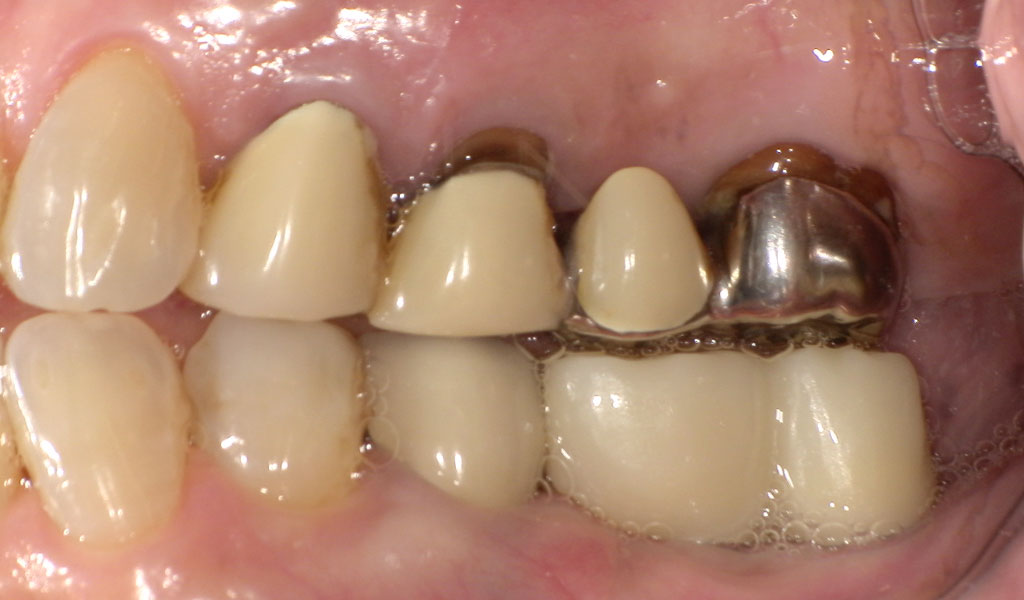

Before1

70代女性・横浜市在住。他院にて20年前に抜歯し放置していたが、インプラント治療を希望されてご来院されました。

術前検査(歯周病菌の検査(PCR検査)を行ったところ、Tf菌の数値が高かったため、投薬及びクリーニングによる歯周病内科治療を実施。